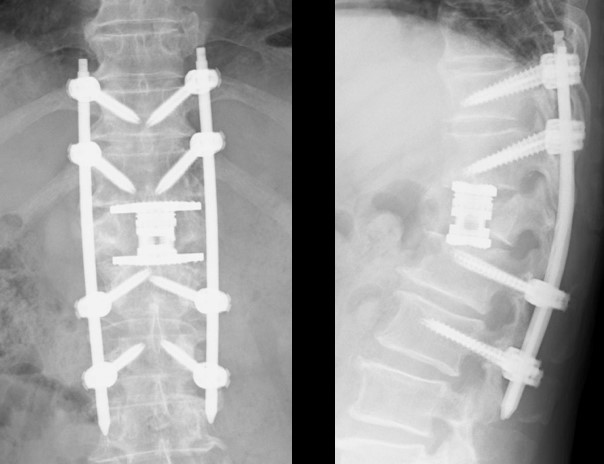

脊椎圧迫骨折の治療 脊椎圧迫骨折の治療には、外科的治療と保存的治療があります。 外科的治療 従来は脊椎固定術で骨同士を固定する手術が主流でしたが、最近ではBKP(Baiion Kyphoplasty)を行う病院も増えています。

脊椎圧迫骨折のための新しい治療法開始について 10年12月27日 脊椎外科 手外科 整形外科 診療科紹介 医療関係者さまへ 関西電力病院